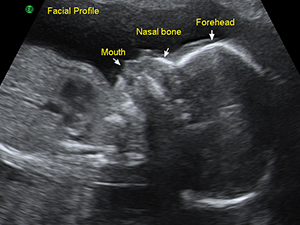

Facial profile in the second trimester